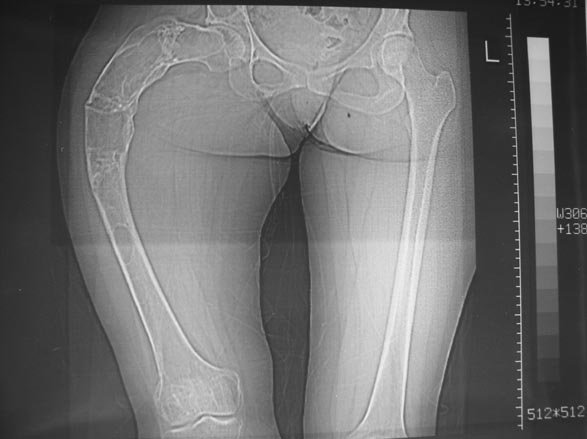

Женщина 28 лет, Больна с 12 летнего возраста, Когда после адекватной травмы получила перелом бедра. На рентгенограммах выявлено какое-то (рентгенограмм и документов нет) изменение бедренной кости, была оперирована, имеется гистологическое заключение - фиброзная дисплазия.дСформировалась деформация бедра. На сегодня - Укорочение 7см. Грубая деформация бедра по типу "пастушьей палки", последний патологический перелом в январе 2004г., консолидировавшийся при консервативном лечении. Имеются грубые изменения и в надвертлужном массиве.-- С уважением, Leonid

Собственно сустав не беспокоит, объем движений полный. По скиаграммам получается, что достаточно одной остеотомии на вершине деформации, чтобы восстановить длину и вывести коленный сустав в нужное положение.

Т.к. укорочение 7 см, то начинать будем с соеотомии и коррекции аппаратом. Спасибо